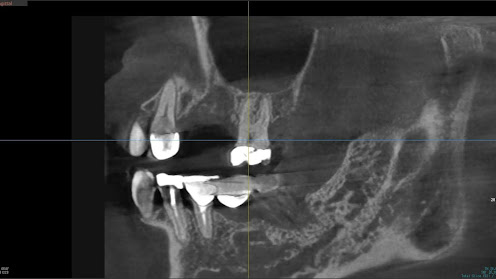

2.右上6番の上顎既存骨2mmのグラフトレスサイナスリフト(骨補填剤を使わない上顎洞挙上術)のケース

Before

枚方市のインプラントの症例

K・Y 様 女性 50代

症状としては、右上6番の歯が歯周病のため、自然に抜けてしまった。

治療法としては、歯周病により、右側6番の上顎骨が吸収して、2mm程度の骨しか残っていなかったため、サイナスリフトが必要であった。通常のサイナスリフトだと時間(時間的には1年から1年半程度かかると考えます。)と費用がかかり、患者様への時間的、肉体的、金銭的負担が大きくなることを考慮して、今回は、インプラントの種類としては、エクストラワイドショートインプラント、術式としては、デンサーバーを使用したグラフトレスサイナスリフトを選択しました。最終補綴物はジルコニアで仕上げています。

結果としては、高度に吸収した上顎骨に対するインプラント治療であったが、グラフトレスサイナスリフトを行うことで、短時間(2か月半程度)で治療を終えることができた。また、サイナスリフトによくある術後合併症である上顎洞炎を起こすことなく、患者様への肉体的な負担を抑えた治療を行うことができた。また、上顎右側6番にインプラント治療できたことにより、咬合が安定するとともに、歯周病にり患している上顎の他の歯に対する負担を少なくすることができた。

治療の期間・回数:約2か月半、6回

治療の価格:363,000円(税込)

治療費の内訳:インプラント基本料(フィックスチャー及び手術費用、投薬費用、レントゲン費用、インプラント上部費用(アバットメントおよびジルコニアクラウンの費用用)330000円(税込み)オプション費用グラフトレスサイナスリフト費用 33000円(税込み)

治療のリスクや副作用:手術後に、痛みや腫れ、出血、合併症などを引き起こす可能性があります。噛む感覚がご自身の歯と異なる場合があります。見た目がご自身の歯と異なる場合があります。手術後にメインテナンスを継続しないと、インプラントが抜け落ちる可能性があります。